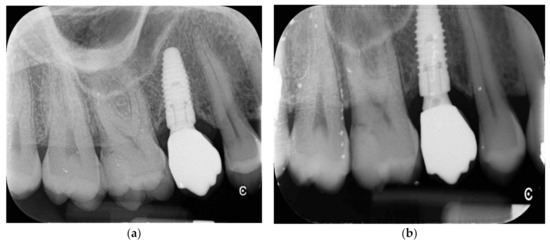

Implant Placement Following Crestal Sinus Lift with Sequential Drills and Osteotomes: Five Years after Final Loading Results from a Retrospective Study

2. Materials and Methods

3. Results